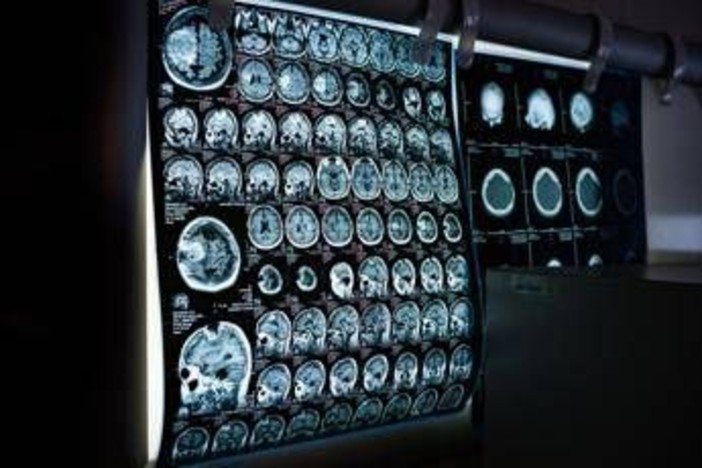

(Adnkronos) - In occasione della Giornata mondiale delle malattie rare 2026, che si celebra il 28 febbraio, la Società italiana di neurologia (Sin) rinnova il proprio impegno nel promuovere attenzione, consapevolezza e azioni concrete per i pazienti affetti da malattie neurologiche rare, un ambito che rappresenta una delle aree più complesse e in continua evoluzione. Queste patologie - informa la società scientifica in una nota - comprendono centinaia di condizioni differenti, spesso di origine genetica, che possono manifestarsi in età pediatrica o adulta e che sono frequentemente caratterizzate da un decorso progressivo e da un importante impatto funzionale. Nel loro insieme, queste patologie interessano un numero rilevante di persone e pongono sfide significative non solo sul piano clinico ma anche organizzativo, sociale ed economico, coinvolgendo l’intero sistema sanitario.

Negli ultimi anni, il panorama delle malattie neurologiche rare è stato profondamente trasformato dalla disponibilità di terapie innovative che stanno cambiando in modo concreto la storia naturale di alcune patologie. Tra queste rientrano, a titolo di esempio, le terapie enzimatiche sostitutive, le terapie di riduzione del substrato, gli oligonucleotidi antisenso, le terapie geniche e altre strategie avanzate attualmente in sviluppo clinico. Questi approcci terapeutici, già disponibili o in fase avanzata di sperimentazione per diverse condizioni neurologiche rare - illustrano i neurologi - rendono ancora più urgente una diagnosi tempestiva e una corretta stratificazione clinica dei pazienti. In molti casi, infatti, l’efficacia delle terapie è strettamente legata alla precocità dell’intervento e alla preservazione delle funzioni neurologiche residue.